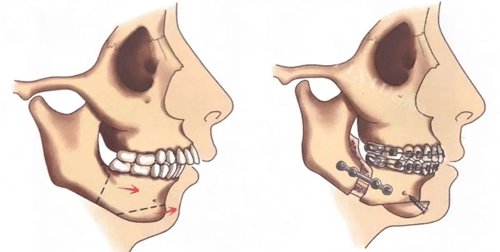

五、成年后的矫正选择

骨骼定型后主要改善牙齿排列,重度骨性问题可能需要正颌手术配合正畸治疗。相比儿童时期,治疗周期更长,结果也有一定局限。